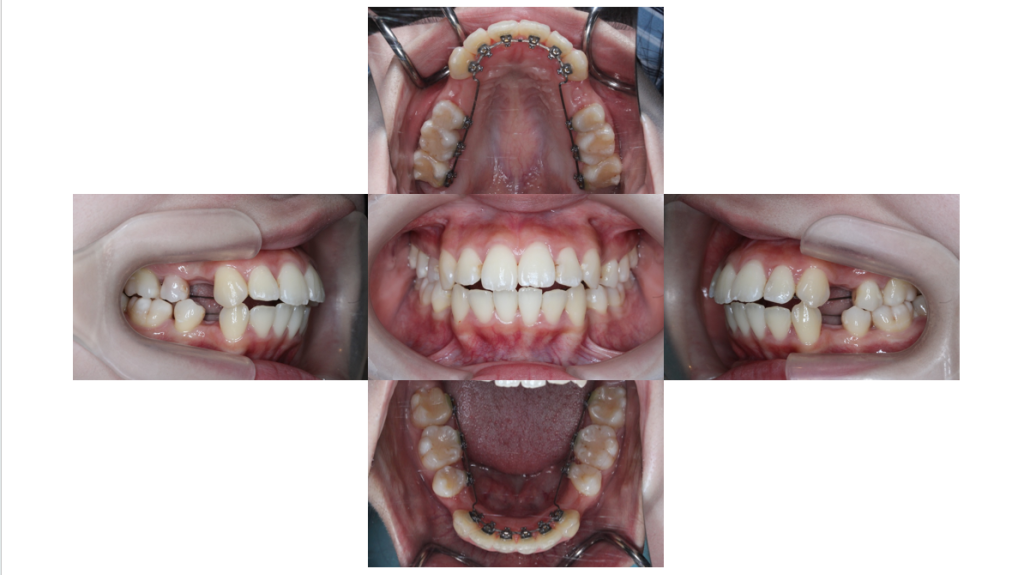

上下装置装着

叢生・裏側矯正の症例上下装置装着直後の口腔内です。